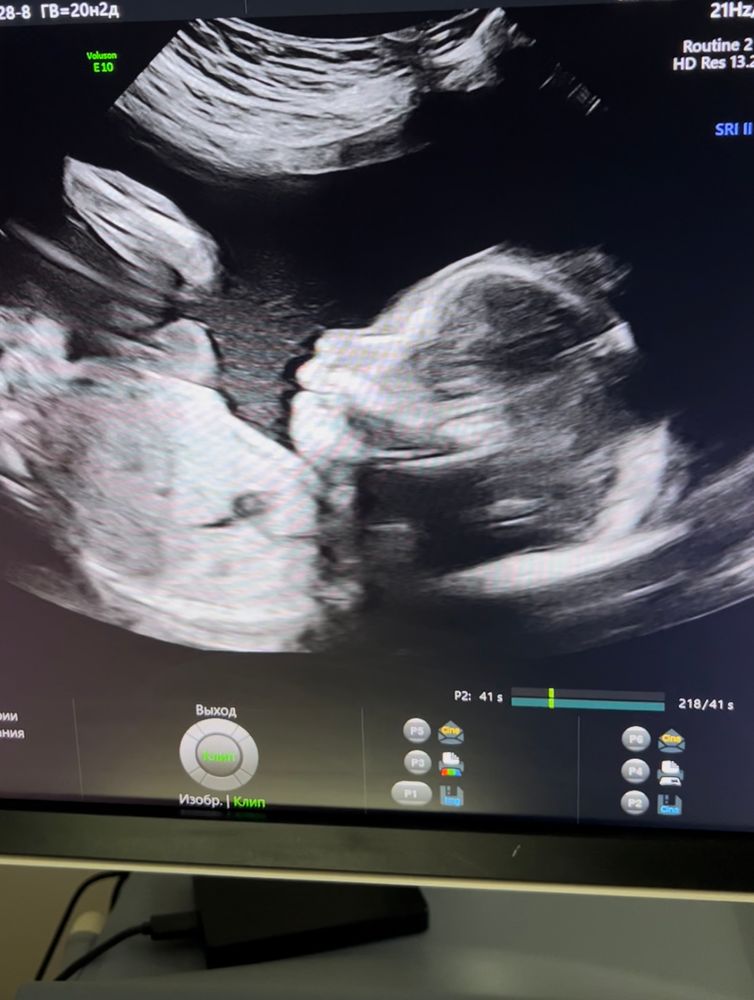

2 скрининг♥️

Какая кнопочка! Поздравляю со 2 скринингом, как же быстро полетело время....

Ещё малюсенькая, а такая красавица и стесняшка 🥰😍🥰